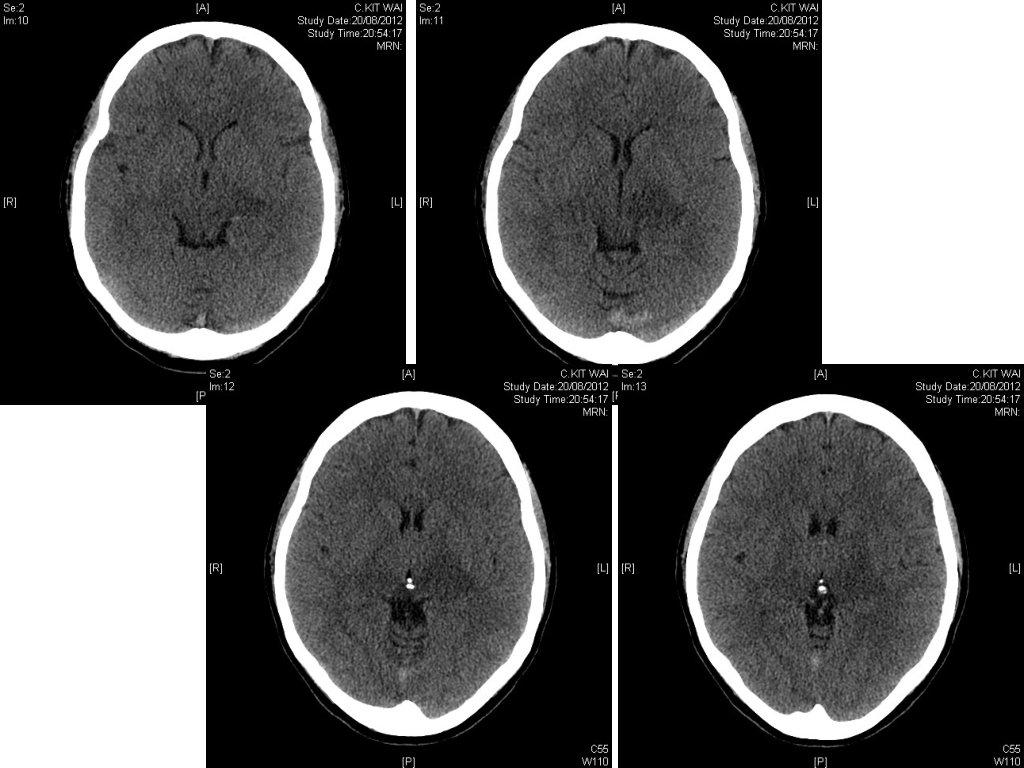

Case 5 • 47/F • Hx of Antithrombin III deficiency • Presented with • Headache for a few days • Right side weakness for a day

• BP 130/80, p 90/min • Afebrile • GCS 13/15; E 3 V 4 M 6 • PERL • Right hemi-paresis with power grade 4/5

1. What is the CT finding? • Hyperdensity at sagittal and transverse sinuses 2. What is the diagnosis? 3. Any laboratory test can help to make the diagnosis? 4. Any further imaging can help to confirm the diagnosis? 5. Name the mainstay of treatment.

1. What is the CT finding? • 2. Hyperdensity at sagittal and transverse sinuses What is the diagnosis? • Cerebral sinus thrombosis 3. Any laboratory test can help to make the diagnosis? 4. Any further imaging can help to confirm the diagnosis? 5. Name the mainstay of treatment.

1. What is the CT finding? • 2. Hyperdensity at sagittal and transverse sinuses What is the diagnosis? • 3. Cerebral sinus thrombosis Any laboratory test can help to make the diagnosis? • D-dimer 4. Any further imaging can help to confirm the diagnosis? 5. Name the mainstay of treatment.

1. What is the CT finding? • 2. Hyperdensity at sagittal and transverse sinuses What is the diagnosis? • 3. Cerebral sinus thrombosis Any laboratory test can help to make the diagnosis? • 4. D-dimer Any further imaging can help to confirm the diagnosis? • 5. MRI +/-MR venogram, or CT venogram Name the mainstay of treatment. • Anti-coagulation therapy